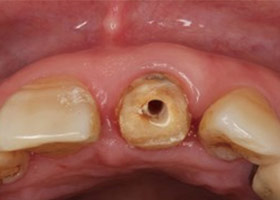

假牙拆除後,因續發性齲齒已深至牙肉下,且牙根明顯鬆動,遂無法保留牙根。

因美觀問題,採取拔牙後立即植牙。(此種治療方式須經醫師評估)